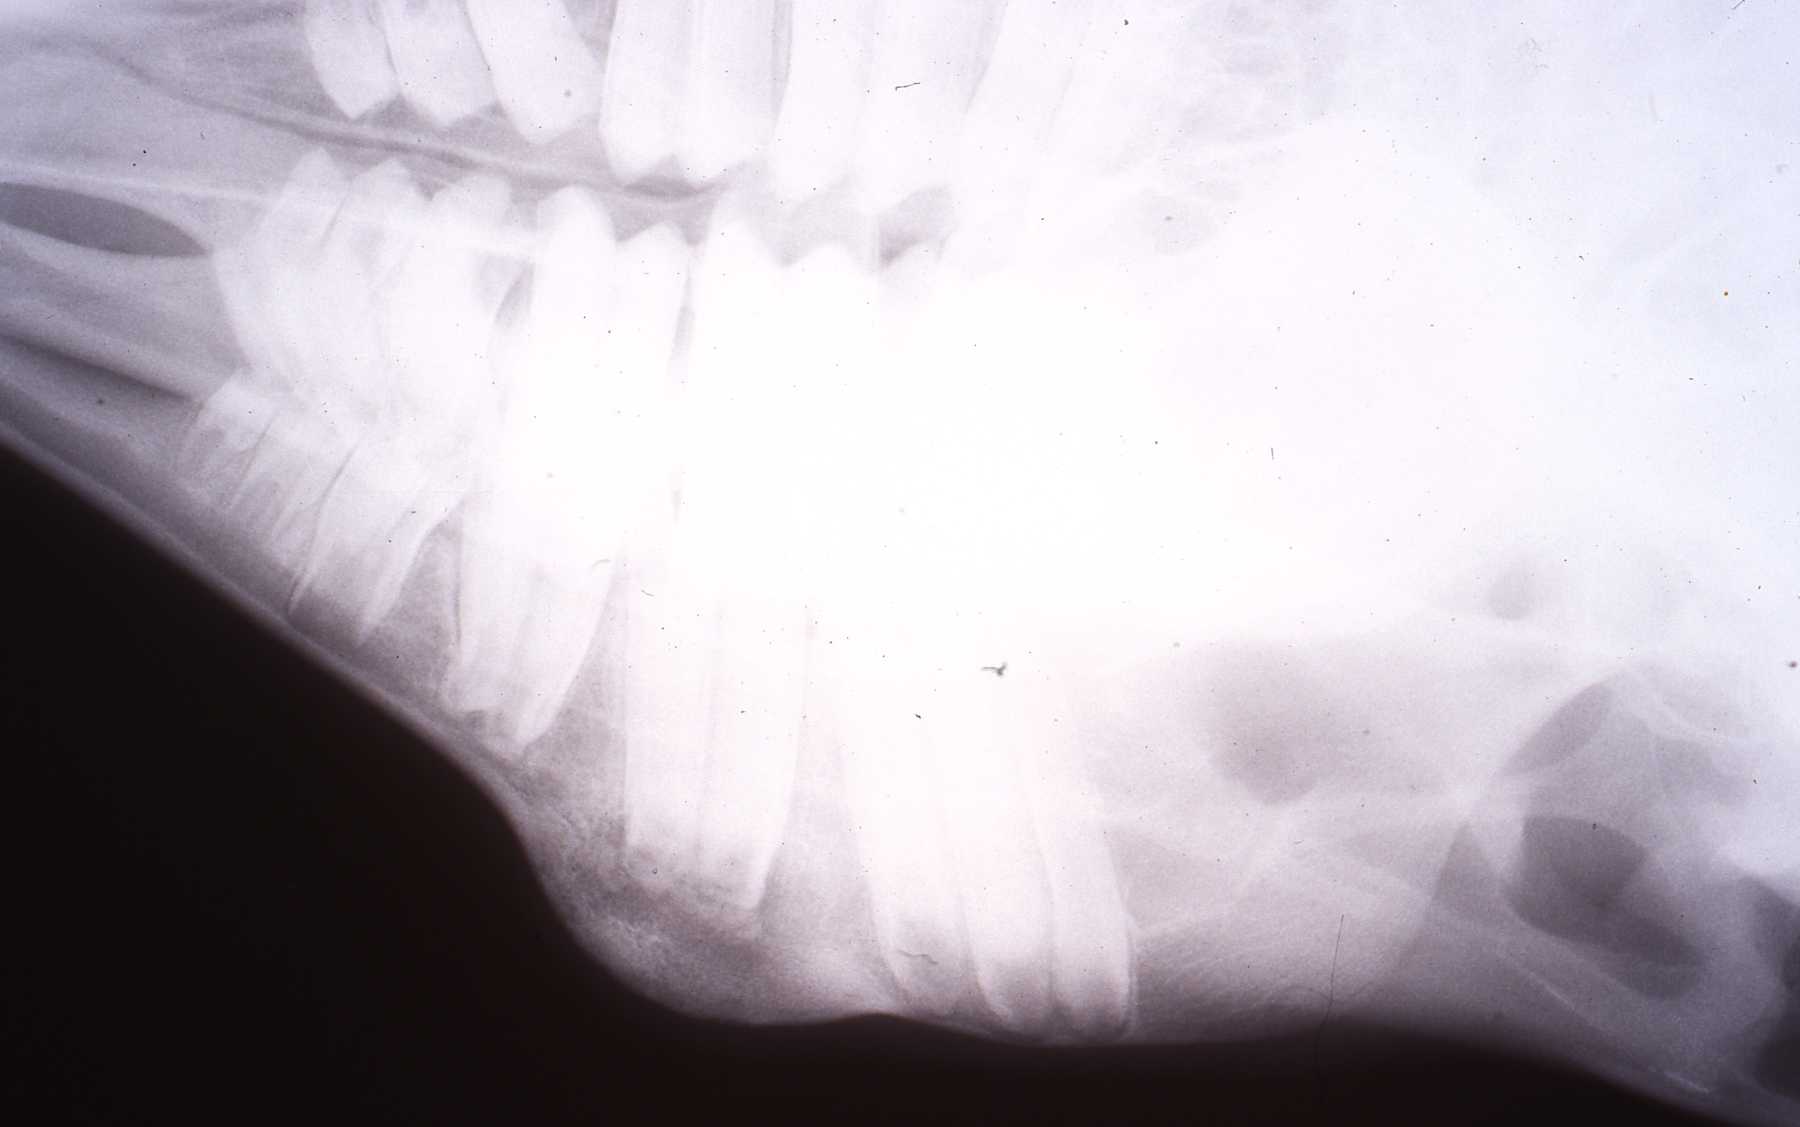

When a mandibular swelling was observed on this Dall sheep ewe by an observant keeper, an anesthesia was scheduled. Under general anesthesia, radiographs revealed periapical lesions and typical bony swelling due to pulpal degeneration, infection and inflammation of the alveolar bone. The intraoral pulp exposure was due to a cusp fracture. After shaving and cleansing the region, the lesion area was entered with a lateroventral approach. After reflecting the overlying skin, the cancellous bone was curetted and cut away with surgical dental burs, always using copious amounts of coolant water. When the tooth apices were exposed a retrograde endodontic procedure was performed. It was restored with amalgam. More recently of course we have utilized EBA and MTA. The cusp fracture was restored. The surgical site was closed after contouring rough bone edges. Oral antibiotics are not an option with ruminants so catching up or squeeze caging it was required to administer injections of antibiotics for several days. Follow up examinations including radiographs revealed healing and bone fill of the mandibular ventral border.

Dall sheep: Radiograph of periapical lesion and bony swelling reaction to abscessed molar